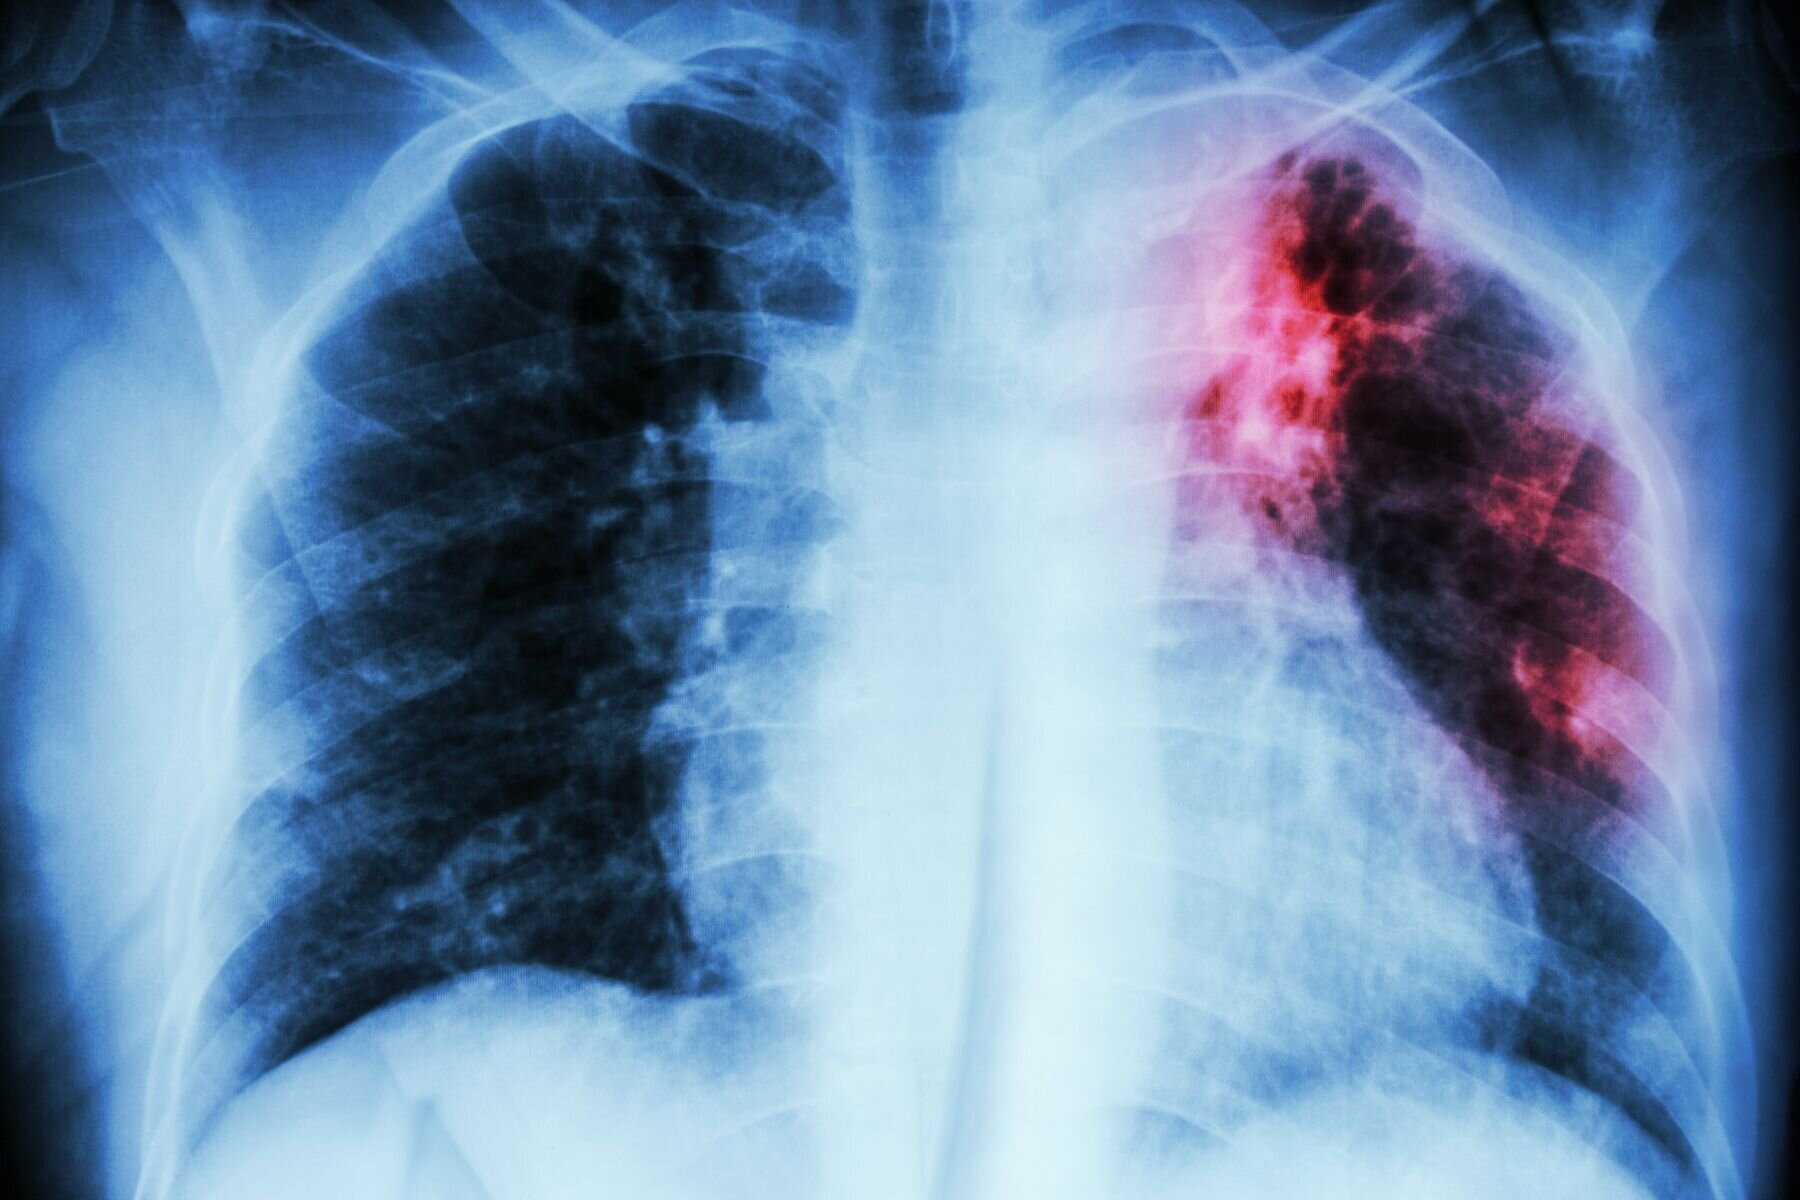

Ni av sakene gjaldt smittsom lungetuberkulose, en gjaldt primær tuberkulose, en mistenkt tuberkulose og en hiv.

Tre av tuberkulosepasientene hadde multiresistent tuberkulose.

– I helt spesielle tilfeller, som ved multiresistent tuberkulose, er ikke personen nødvendigvis ferdigbehandlet etter et år, og kan fortsatt spre smitten. Det har ikke skjedd mange ganger, men det er svært viktig at vi vet hva vi skal gjøre i disse tilfellene, sier Holst.

Hun opplyser om at det ligger an til at meslinger og rubella kommer inn på listen over allmennfarlige smittsomme sykdommer, mens regelverket om tvangsisolasjon og medikamentell behandlig under tvang gjelder for de svært alvorlige allmennfarlige smittsomme sykdommene, som multiresistent tuberkulose, sier hun.